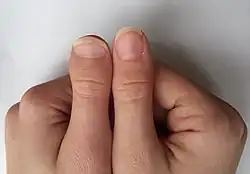

| Unilateral brachydactyly type D in an adolescent female | |

Brachydactyly type D, also known as murderer's thumb,[3][1] stubbed thumb,[5][6] spoon thumb, power thumb or short thumb,[5][6] is a genetic trait recognised by a thumb being relatively short and round with an accompanying wider nail bed. The distal phalanx of such thumbs is approximately two-thirds the length of full-length thumbs. It is the most common type of shortness of digits (brachydactyly), affecting approximately 2% of the population. It is associated with the HOXD13 gene, located on chromosome 2q31.1.[7]

Brachydactyly type D is a skeletal condition that exhibits a “partial fusion or premature closing of the epiphysis with the distal phalanx of the thumb,” according to Goodman et alia (1965).[6] J.K. Breitenbecher (1923) found that the distal phalanges of short thumbs were one-half the length of full-length thumbs, while R.M. Stecher (1957) claimed that it is approximately two-thirds. The condition may be unilateral (affecting one thumb) or bilateral (affecting both).[6]